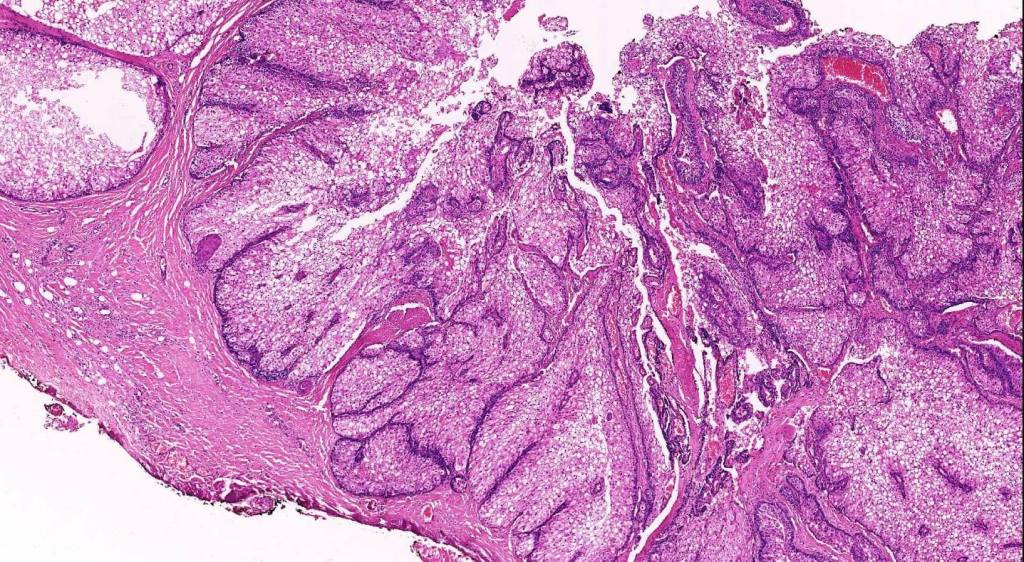

Histological features

•Variable continuity with epidermis

•Multinodular with surrounding collagenous stroma

•Random distribution of basaloid cells & sebocytes (<50% sebocytes)

•Duct formation, often with holocrine secretion generally present

•Mitoses sparse to conspicuous

•Absent peripheral palisading & retraction artifact

•Cystic variant

•Subtypes include rippled pattern, carcinoid-like & reticulated